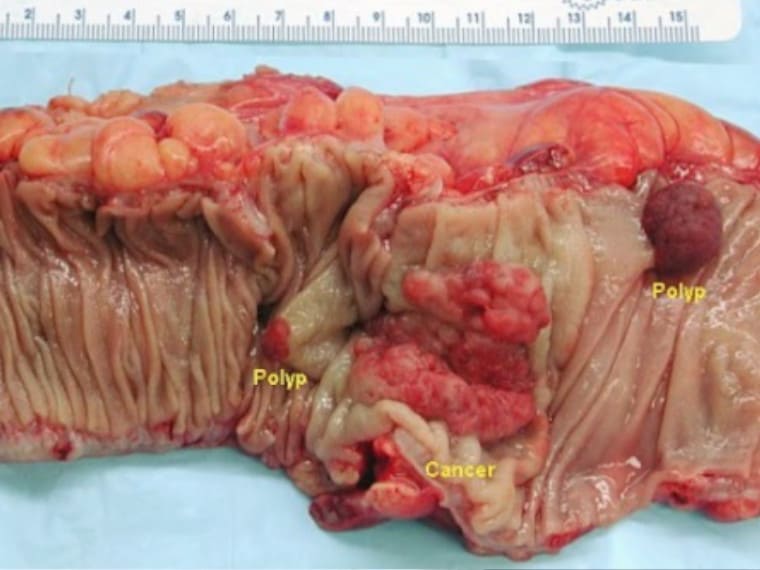

De las hemorroides al cáncer de colon 1 paso

Mucha gente ignora el problema de las hemorroides, a pesar de sus graves riesgos para la salud.

Cáncer de intestino en formas más avanzadas.